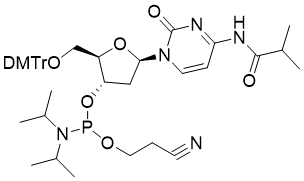

馬鞍山致研生物醫(yī)藥科技有限公司成立于馬鞍山市鄭浦港新區(qū)現(xiàn)代產(chǎn)業(yè)園。公司專(zhuān)注于生物小分子、醫(yī)藥中間體相關(guān)產(chǎn)品的研發(fā)和生產(chǎn),產(chǎn)品主要包括DNA亞磷酰胺單體、RNA亞磷酰胺單體、特殊單體以及按照客戶(hù)要求定制的RNA和DNA,并且公司提供定制合成等方面的研究服...

馬鞍山致研生物醫(yī)藥科技有限公司成立于馬鞍山市鄭浦港新區(qū)現(xiàn)代產(chǎn)業(yè)園。公司專(zhuān)注于生物小分子、醫(yī)藥中間體相關(guān)產(chǎn)品的研發(fā)和生產(chǎn),產(chǎn)品主要包括DNA亞磷酰胺單體、RNA亞磷酰胺單體、特殊單體以及按照客戶(hù)要求定制的RNA和DNA,并且公司提供定制合成等方面的研究服...